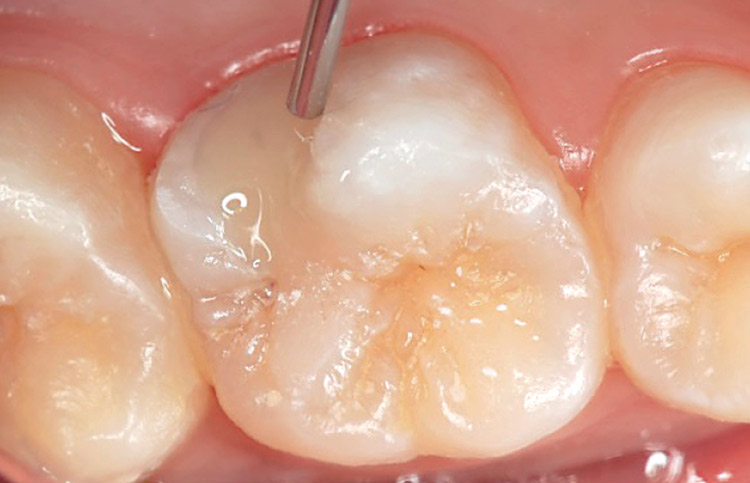

上顎第一大臼歯口蓋側のう蝕。初診時の所見は、エナメル質に点状に開いた小さいう蝕と思えたが、X線所見から象牙質まで深く広がるう蝕と診断。症状は冷水痛があった。MIに沿った窩洞形成を行い、バルクベース付属のボンディング材バルクベースライナーを用いて20秒間セルフエッチング処理を行う。なお、症状が強く、術後疼痛等のリスク軽減を主目的とする場合には、良質な接着層の形成が可能な、TBB系ボンディング材( スーパーボンド Dライナーデュアルなど)を用いることを勧める。十分に乾燥後、バルクベースライナーの光重合硬化。続いて、バルクベースペーストを直接一括充填する。バルクベースペーストはフロー性によりハイフローとミディアムフローの2タイプがあり、用途に応じて使い分けが可能である。症例の場合は、上顎のため垂れにくいミディアムタイプを使用した。バルクベースペーストの光重合硬化。

低収縮型フロアブルレジン・バルクベースを用いた裏層の完了。最後に症状がないかを確認し、最終充填にはファンタジスタやメタフィルFloなどを充填し、咬合調整、仕上げ研磨を行う。充填後3ヵ月、冷水反応等の症状はない(図5-1〜9)。

図5-9 充填後 3ヵ月